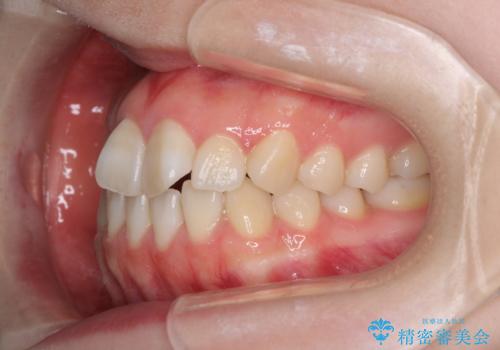

- 前歯の捻れと、ちょっとした出っ張りを気にして来院された患者様です。

歯と歯の間を削る(IPR)ことでデコボコを解消し、インビザラインで整えることとしました。

インビザライン治療特有の奥歯が接触しない時期が続き、当初予定よりも期間がかかりましたが、最終的には安定した咬み合わせと、整った前歯になりました。